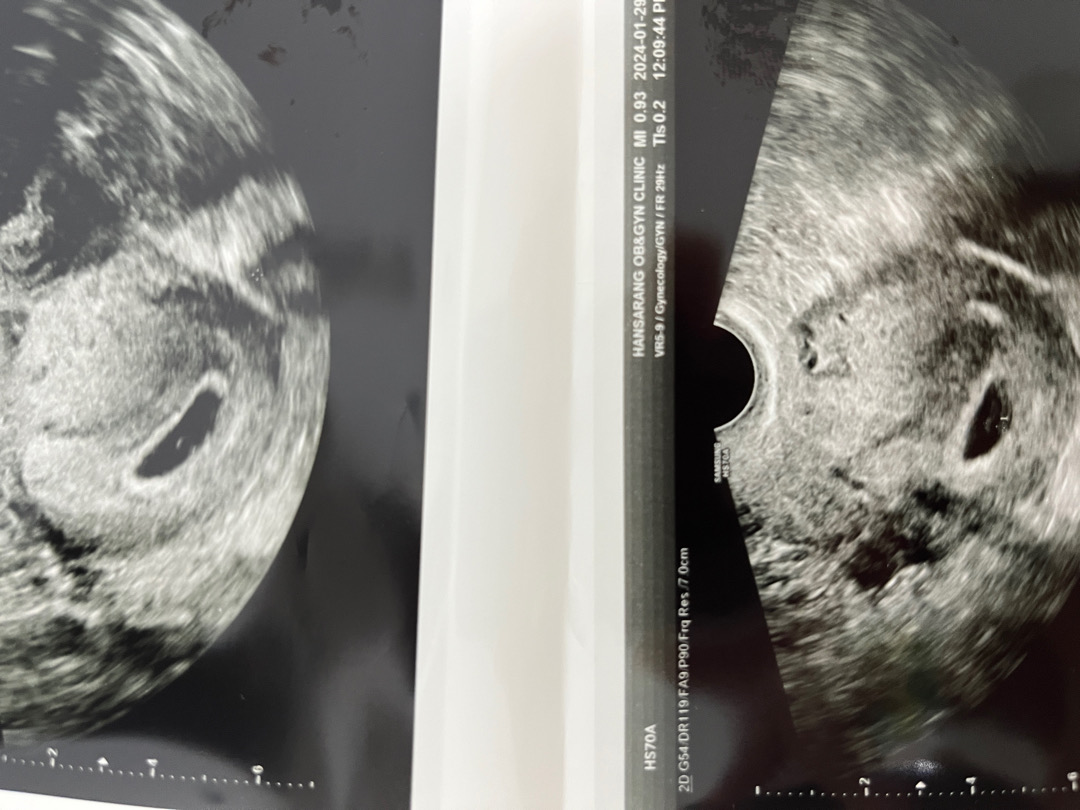

마지막생리 기준일로는 6주차라고 뜨는데 실제 초음파 상으로는 배란이 많이 늦어진 것 같다고 하시면서 4주차 정도라고 하셨는데요. 아주 희미하게 난황이 보인다고 하셨는데(3mm) 일주일 뒤쯤에 배아를 볼 수 있을까요?ㅜㅜㅜㅜㅜ 처음이라 걱정만 앞서고 아무것도 모르겠네용.. 원래 난황부터 보이고 그 다음에 애기가 보이나요??